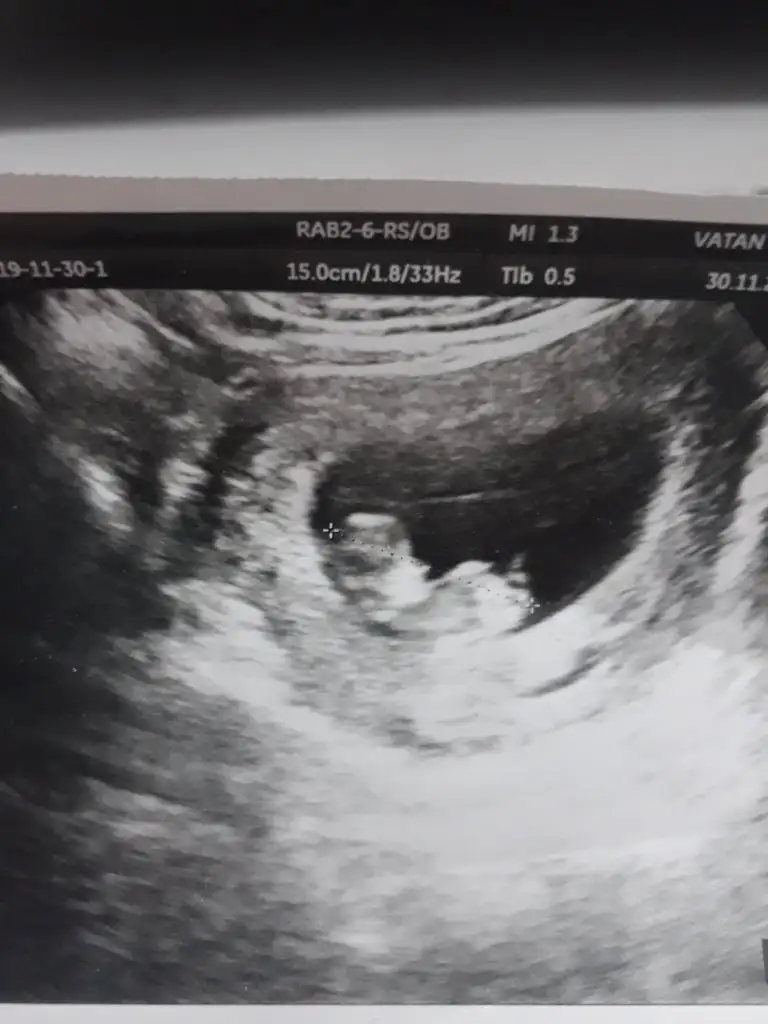

Doğru yere mi yazdım bilmiyorum ama benim bebeğime de bakar mısınız Kızlar 14 haftalık görüntü

• 32E4313E-FA5F-4A92-9B54-C9014FB13699.webp

32E4313E-FA5F-4A92-9B54-C9014FB13699.webp

14,3 KB · Görüntüleme: 51